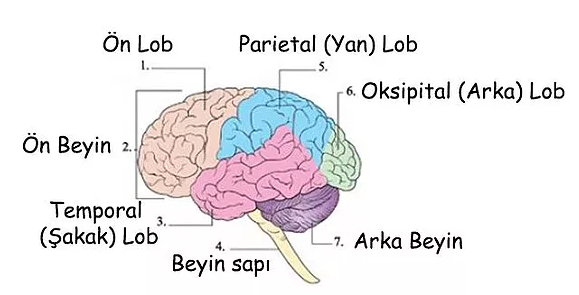

Beyin tümörü uyku hali. Yetişkinlerde ikincil beyin tümörleri birincil beyin tümörlerinden çok daha yaygındır. Ancak şikayetler çok daha çeşitlilik gösterebilir. 1925 yılından beri bilinen bu beyincik tümörü çok ayrı hücresel ve klinik özellikeri olan ve oldukça habis karekterli bir beyincik tümör tipidir beyinciğin çocuklarda en sık tümörü olup tüm primer beyin tümörlerininin 4 10 teşkil ederler. Patoloji alındı ondada tam teşhis konulmadı.

Uykuyu kontrol eden sinirler beyin sisteminde yer aldığı için sürekli uyku problemini çözmek için nöroloji bölümüne gitmeniz gereklidir. İkincil beyin tümörleri en sık kanser öyküsü olan kişilerde görülür. Denge kaybı uyku hali gözde görme sorunları duyma sorunları el ya da ayaklarda his sorunları ruhsal değişiklikler halüsinasyonlar görebilir yemek yeme sorunları yutkunma sorunları yemek yeme sorunları halsizlik trombosit düşüklüğü lökosit. Sadece uyku hali be yorgunluğu vardı.

Sonrasında bulantı kusma şuur dalgalanmaları uyku hali baş dönmesi ve nöbet geçirme vücudun farklı bölgelerinde kuvvetsizlikler iştahsızlık unutkanlık gelmektedir. Bunların en başında yeterince uyumamaktır. Ancak çocukluk yaşı tümörlerin 15 20 sini teşkil etmektedir. Beyin tümörü uyku yapar mı.